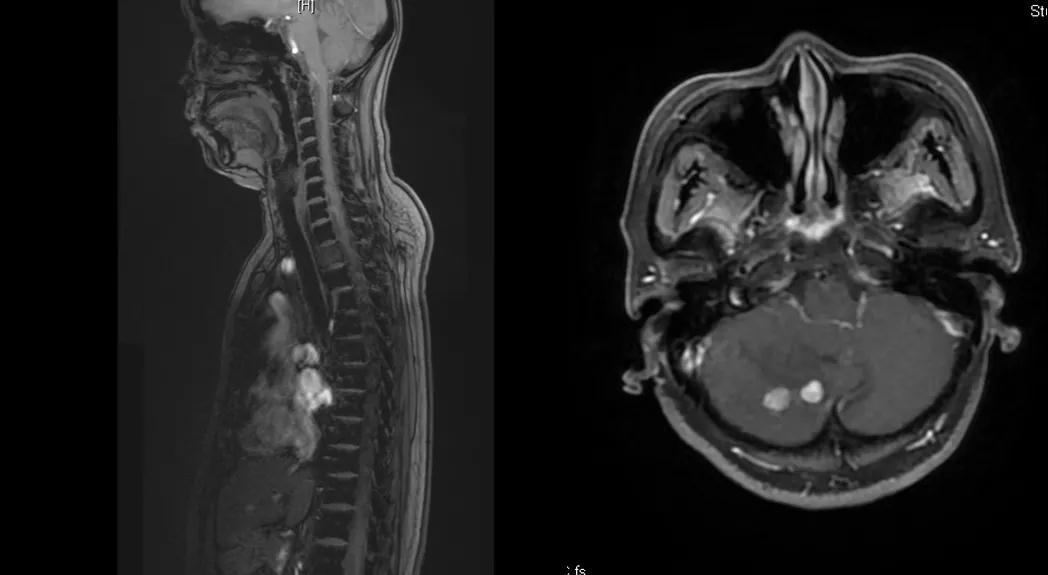

给予T-DM1治疗。治疗6个月后复查MR显示脑、肝、骨转移瘤均较前明显缩小,达到部分缓解(PR)(图2)。目前PFS已达10+个月。

图2

患者为ⅢA期(cT3N1M0)、三阳性乳腺癌,经AC-TH新辅助治疗达到降期(ypT2N0M0)。患者内分泌+抗HER2辅助治疗结束6个月时出现转移进展(脑、肝、骨),给予THP一线治疗,因无法耐受毒副作用而改为T-DM1,治疗6个月达到肝、脑、骨转移PR,患者目前中位PFS已超过10个月,T-DM1治疗过程中仅出现轻度CIT,且可自行恢复。